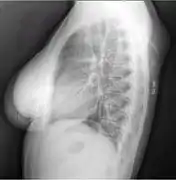

A physical exam is typically the easiest way to diagnose it. Rarely, a tissue biopsy or imaging may be required. The imaging modality of choice is magnetic resonance imaging (MRI) because it has superior sensitivity of distinguishing it from liposarcoma as well as mapping the surrounding anatomy.[22]

Lipomas are rarely life-threatening, and the common subcutaneous lipomas are not a serious condition. Lipomas growing in internal organs can be more dangerous; for example, lipomas in the gastrointestinal tract can cause bleeding, ulceration, and painful obstructions (so-called "malignant by location", despite being a benign growth histologically).[33][34] Malignant transformation of lipomas into liposarcomas is very rare, and most liposarcomas are not produced from pre-existing benign lesions.[28] A few cases of malignant transformation have been described for bone and kidney lipomas,[35][36] but it is possible that these few reported cases were well-differentiated liposarcomas in which the subtle malignant characteristics were missed when the tumor was first examined.[37] Deep lipomas have a greater tendency to recur than superficial lipomas because complete surgical removal of deep lipomas is not always possible.[37][38]